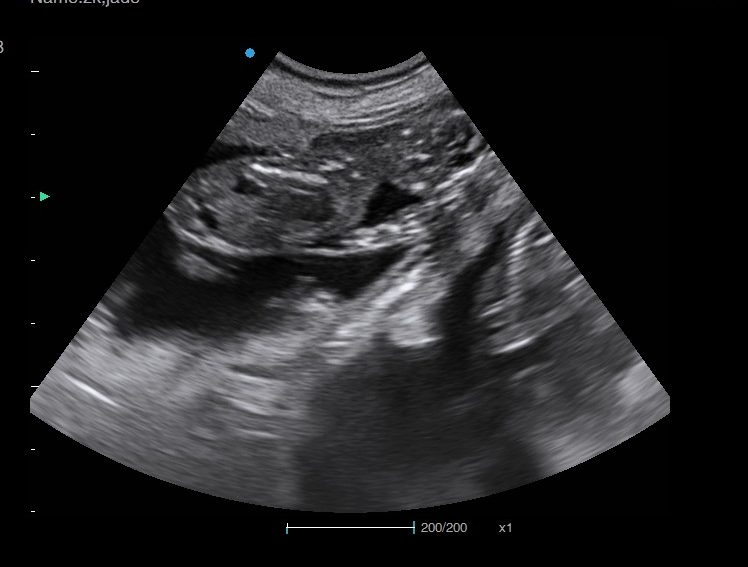

Ultrasound pregnancy scanning is a safe, non-invasive way to confirm pregnancy in dogs and cats, offering breeders and pet owners peace of mind and vital information to support responsible care. It allows us to detect gestational sacs, assess foetal development, and estimate litter size—all while ensuring the wellbeing of the animal.

Pregnancy can sometimes be detected as early as Day 18 post-mating, but scanning at this stage is not routinely recommended. Embryos are still developing and may not be clearly visible, and there is a natural risk of embryo resorption, which can lead to misleading or inconclusive results.

For the most accurate and reliable scan, we advise booking between Day 25 and Day 32, when pregnancy is more easily confirmed and foetal structures are clearer. If an early scan is performed and no pregnancy is detected, we offer a FREE complimentary re-scan after 7 days at the clinic to ensure clarity and support informed decision-making.

Our approach balances early insight with ethical care—always prioritizing the comfort of the animal and the accuracy of the results.